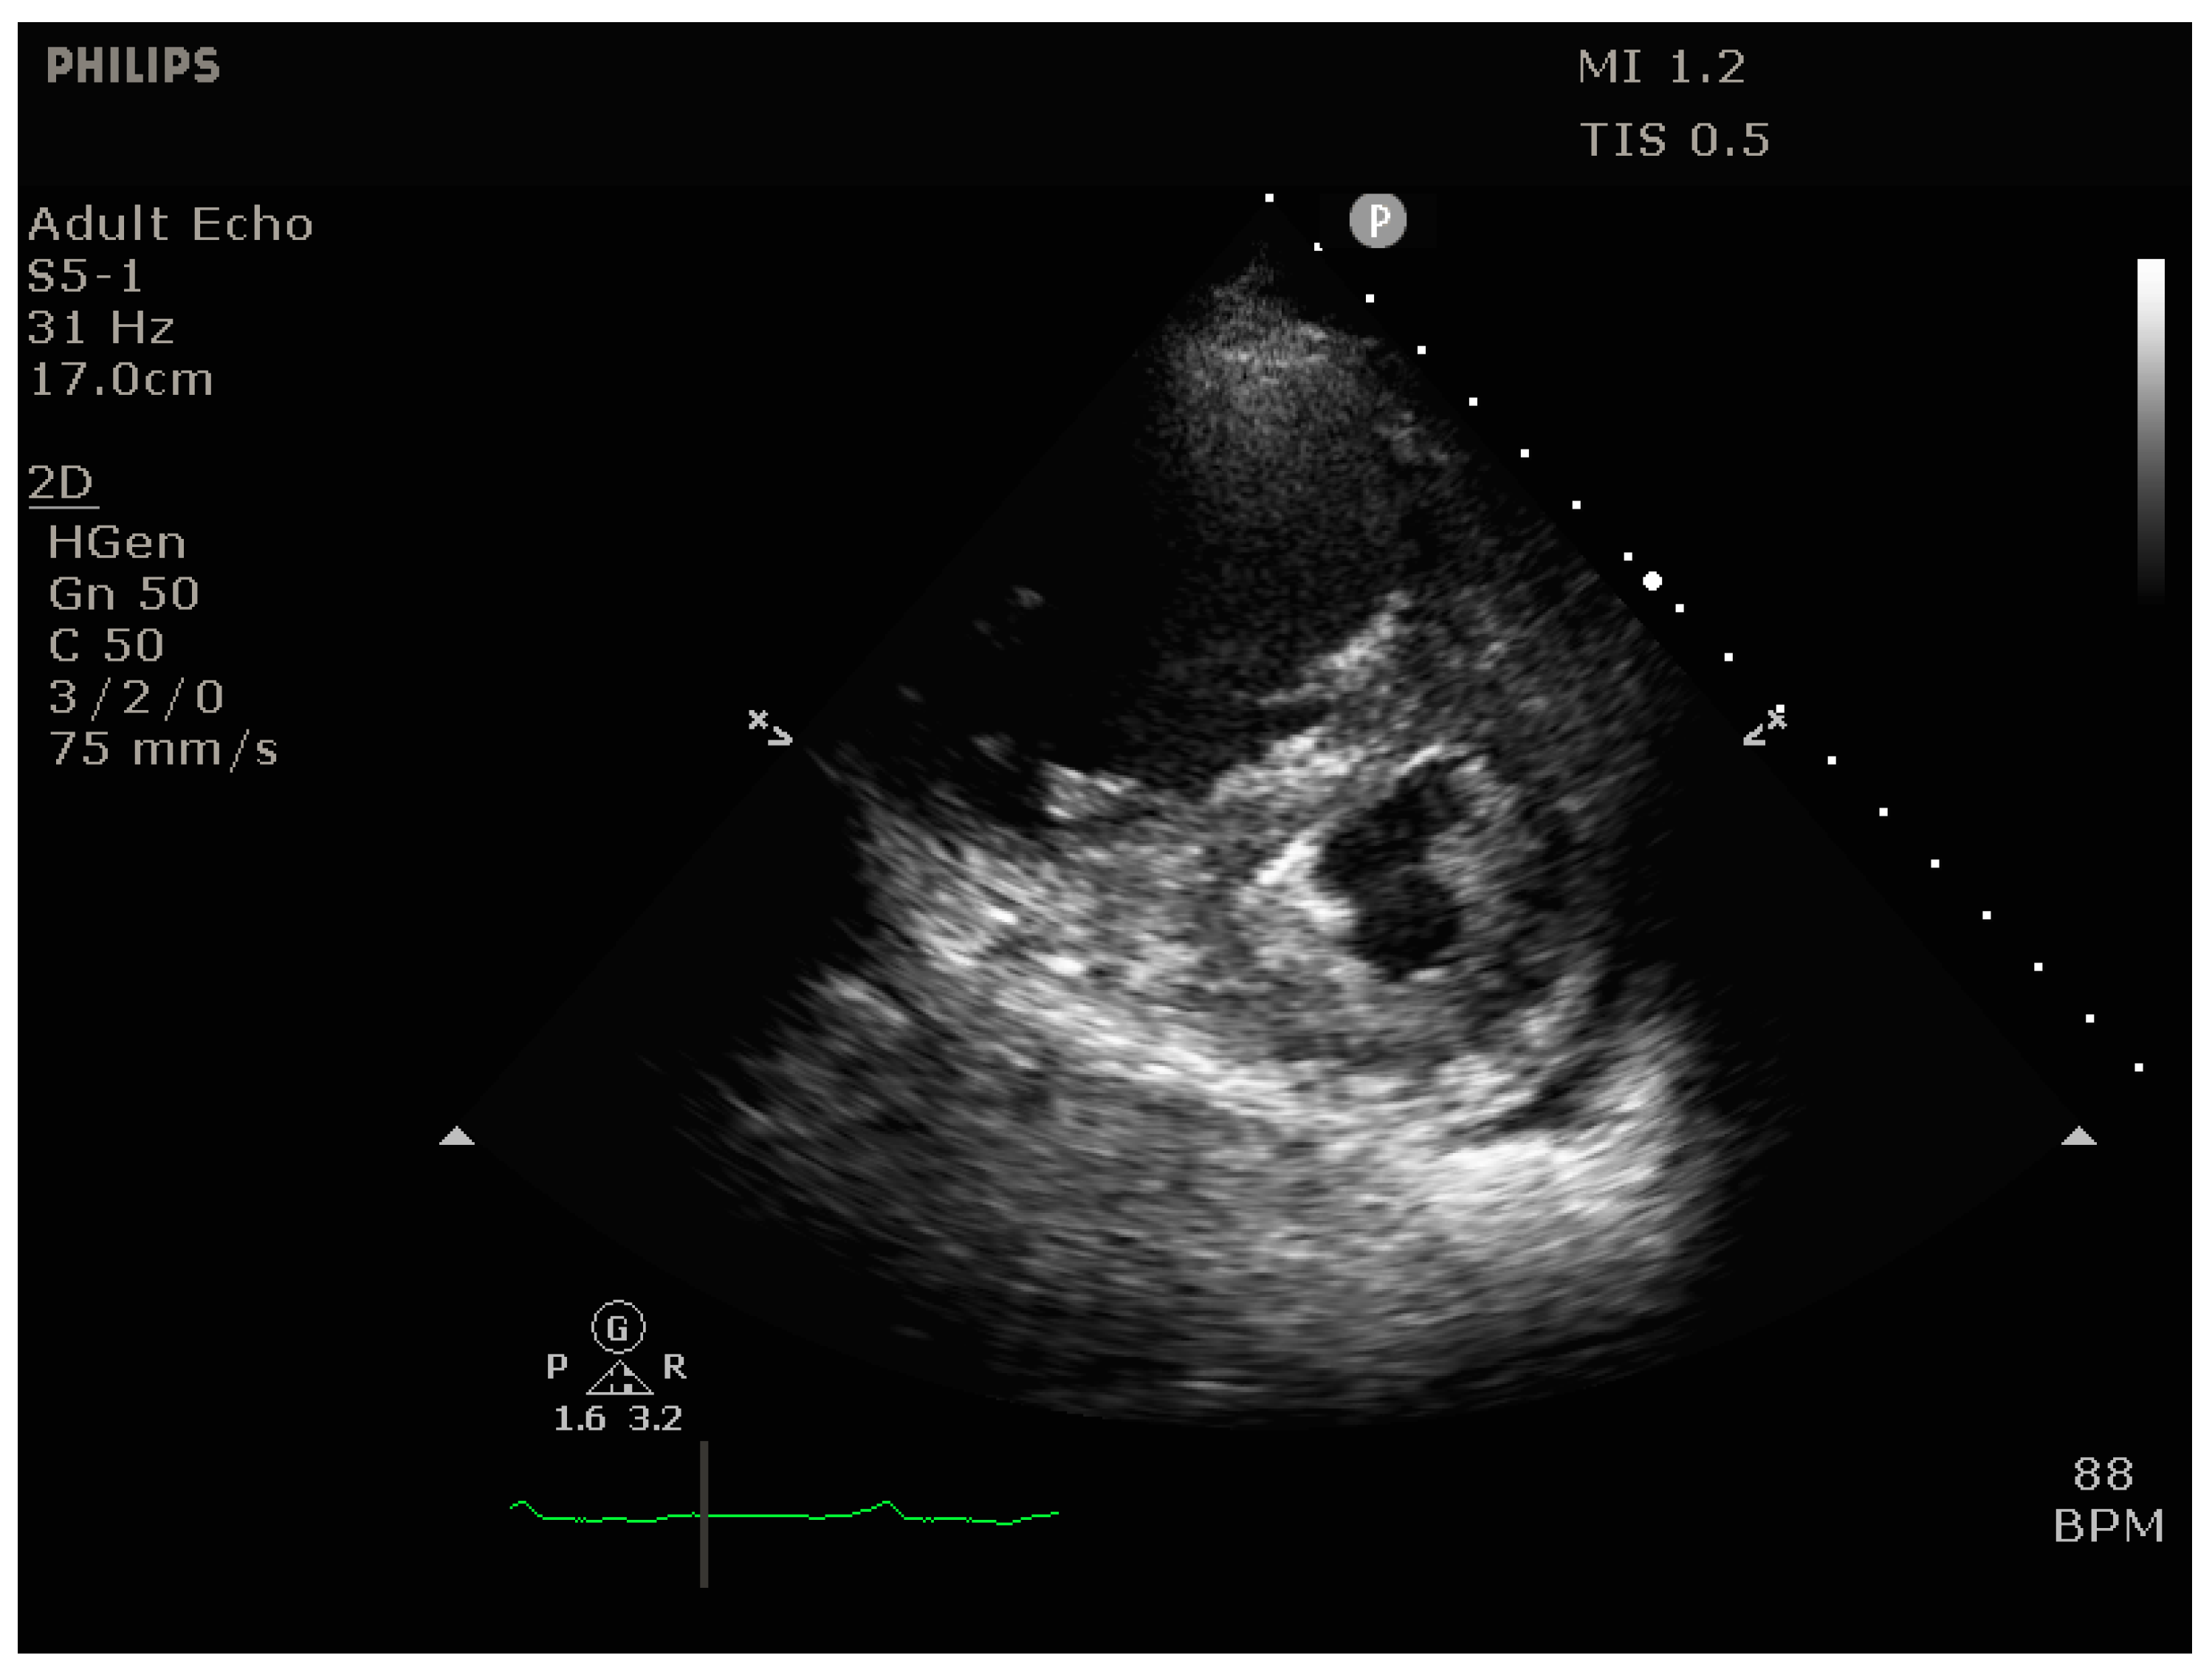

4.2.2. Echocardiography

- Signs of RV dilation: D-shaping, increased RV:LV ratio, tricuspid regurgitation

- Signs of impaired RV systolic function: reduced tricuspid annular plane systolic excursion (TAPSE)

- Signs of elevated RV preload (plethoric inferior vena cava [IVC])